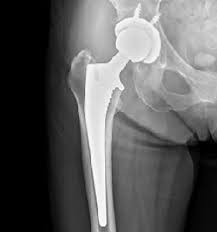

この筋肉内への脂肪浸潤は、全身にわたる筋肉の質を損なう全身性の問題であり、下肢の関節変形(変形性股関節症、変形性膝関節症)を発生させて、関節手術が必要な最悪な状況へと陥れます。

肥満による関節への負荷が増大し、“股関節・膝関節・足関節の軟骨の損傷→関節変形”を発症し、歩行が困難になったり、人工関節置換術などの人工関節挿入手術が必要になってしまいます。